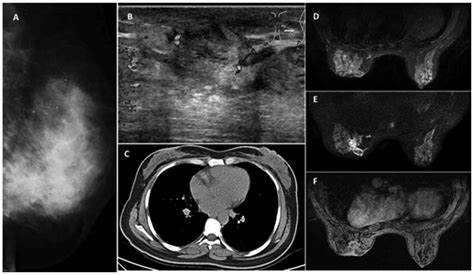

• Imaging Tests: Imaging tests such as mammography, ultrasound, or MRI may be used to visualize the affected tissue and rule out other conditions.